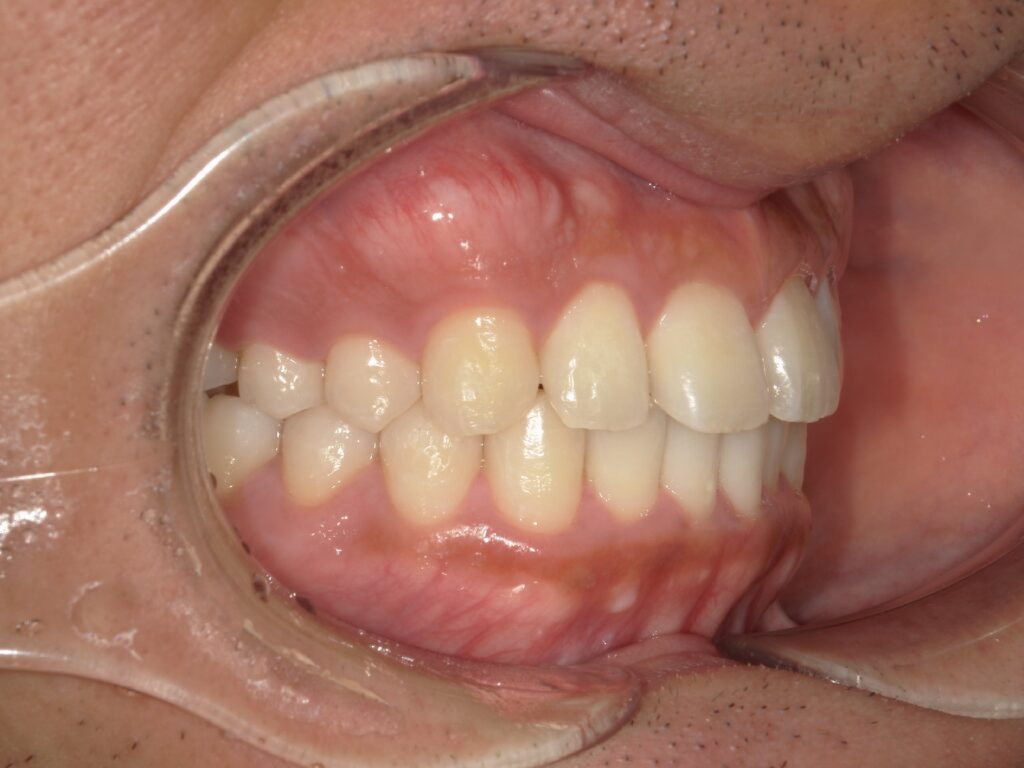

下記のケースでは、奥歯の噛み合わせが悪くなかったことから、患者様の希望もあり、部分矯正で対応いたしました。

上顎の前歯が大きく突出しています

明らかに前歯の突出感が改善し、患者様はこの時点でとても喜ばれていました

矯正治療終了時 部分矯正ということもあり、短期間で矯正治療を終了することができました